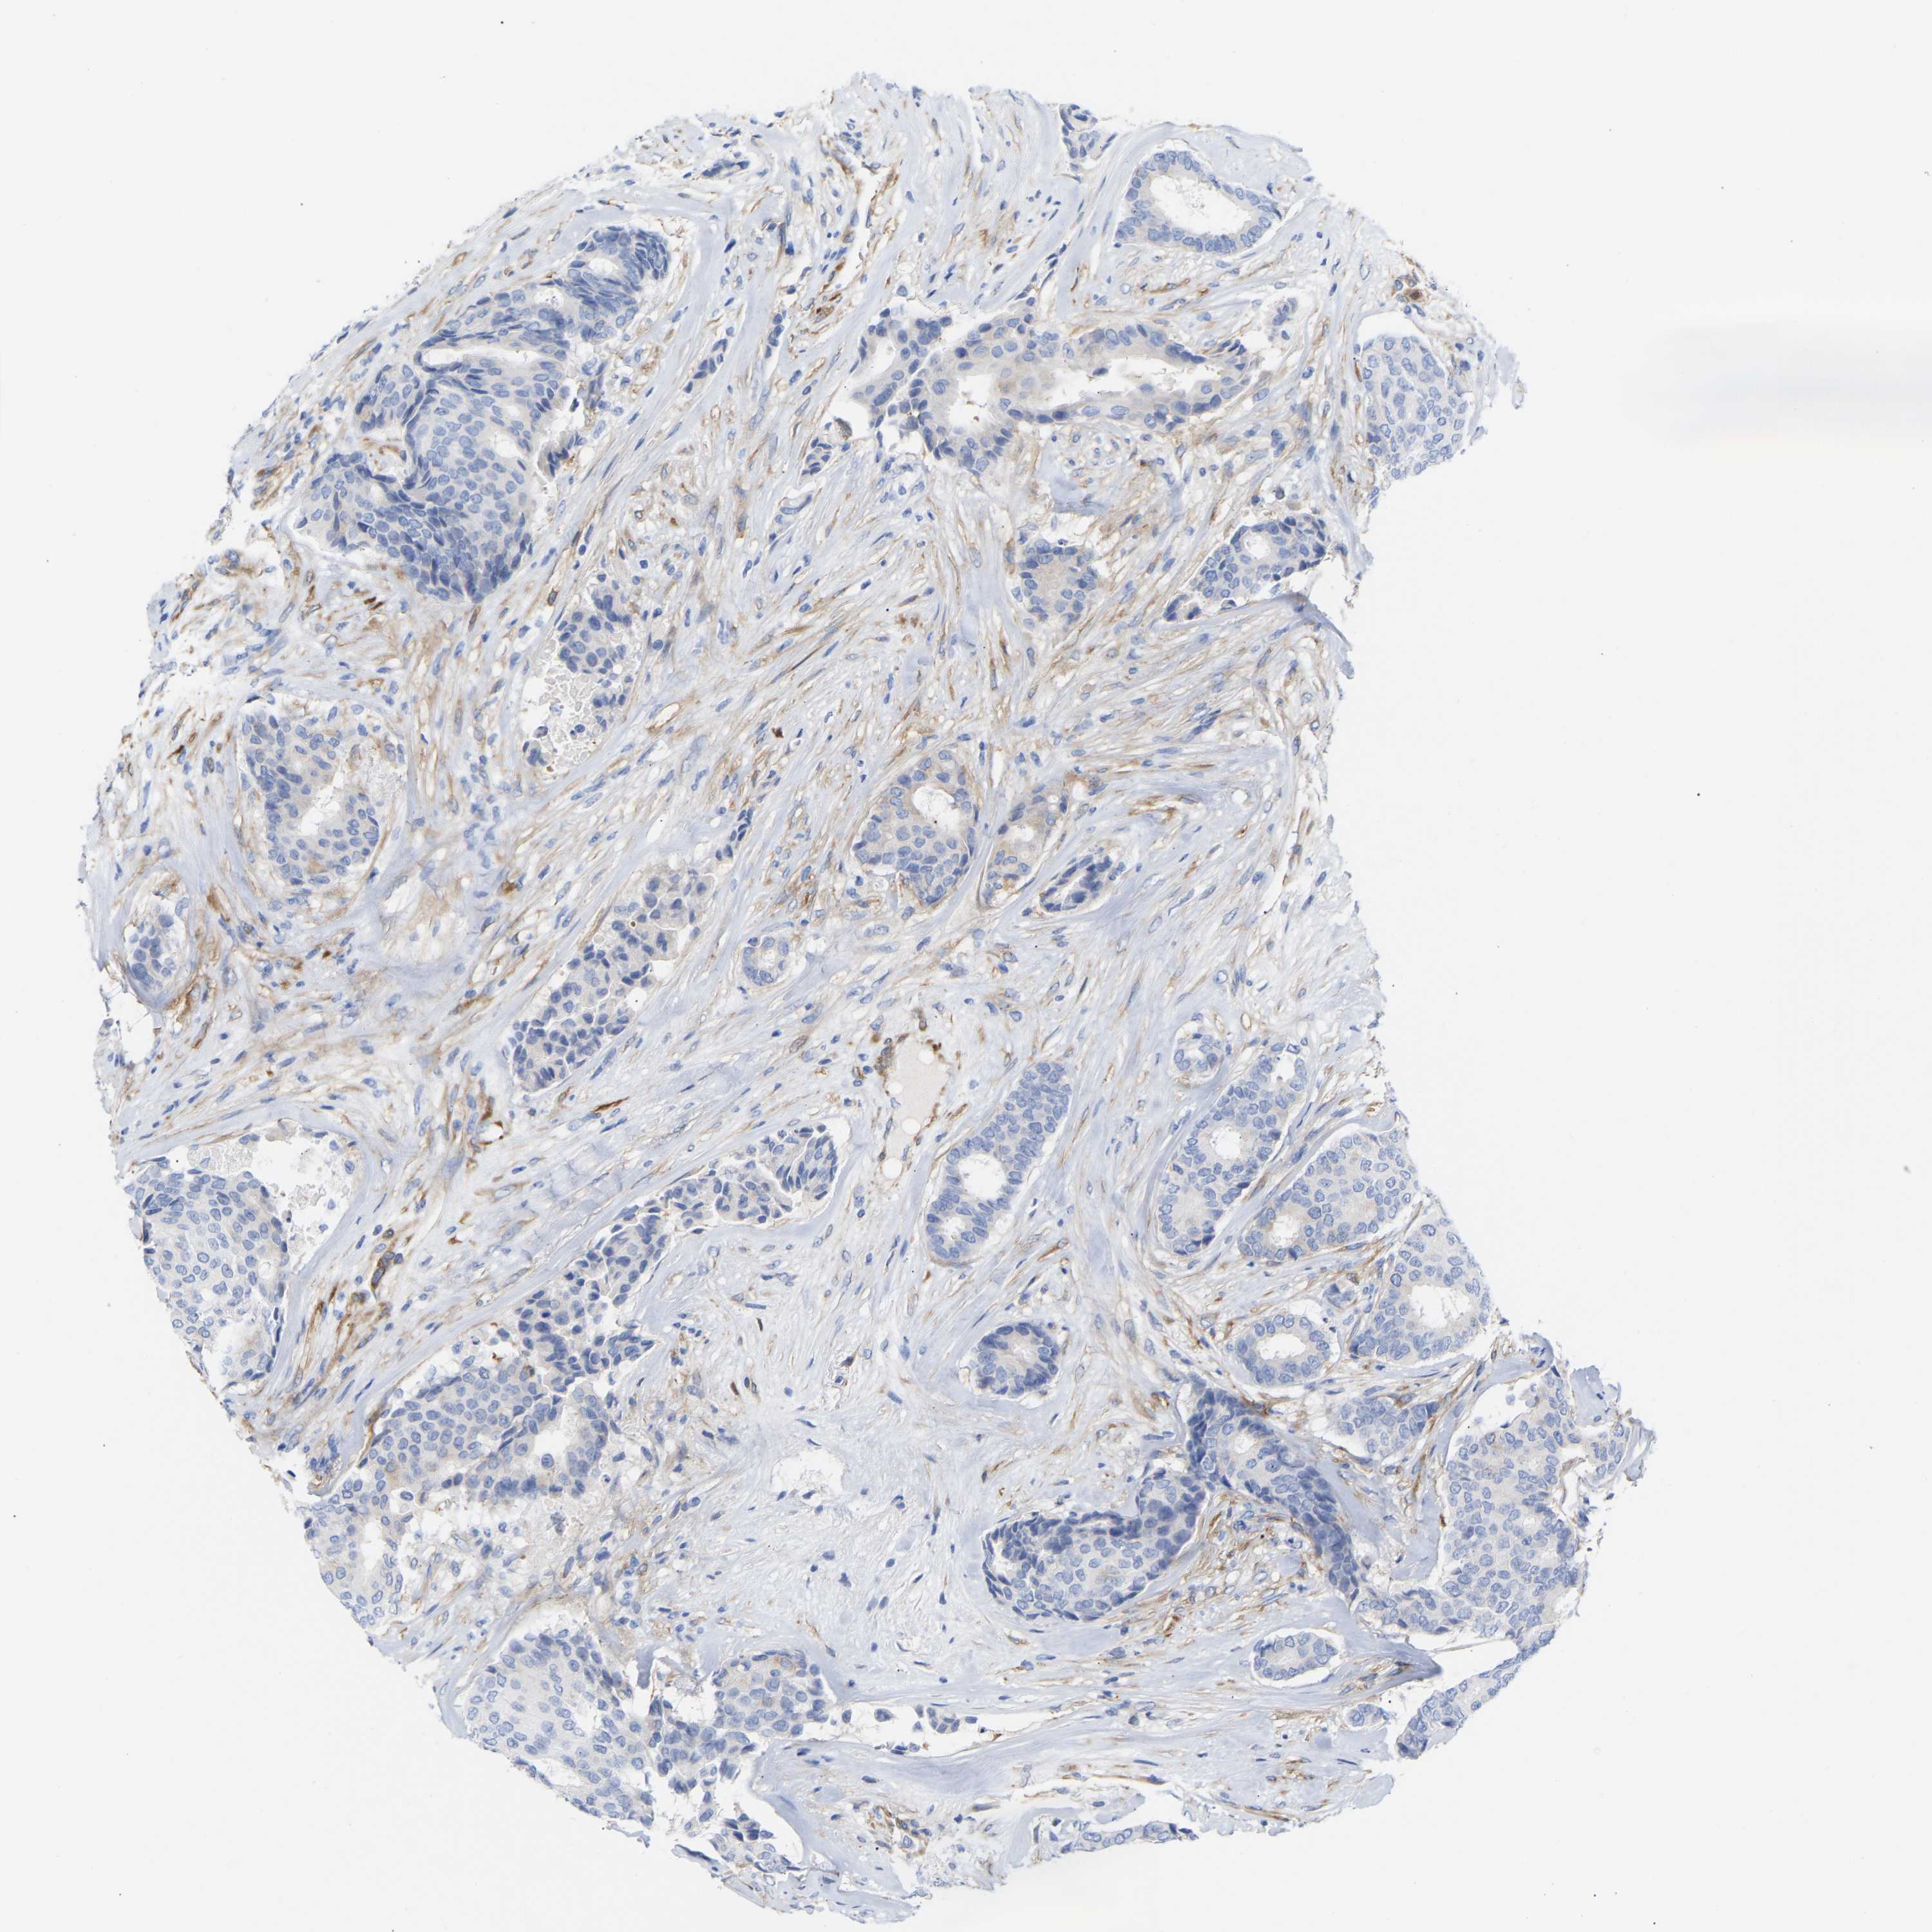

CANCER BREAST CANCER Show tissue menu

BRCA TCGA BRCA VALIDATION PROTEIN EXPRESSION

Breast cancer

Human cancer